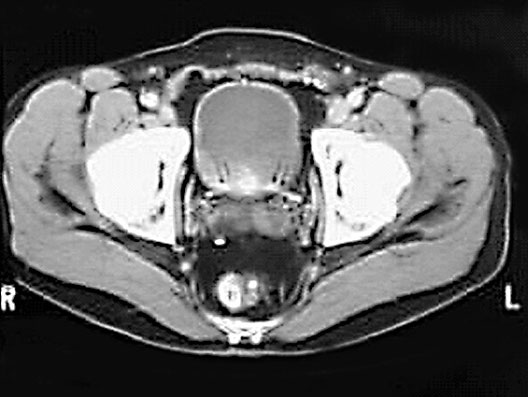

Bladder

1. Bladder